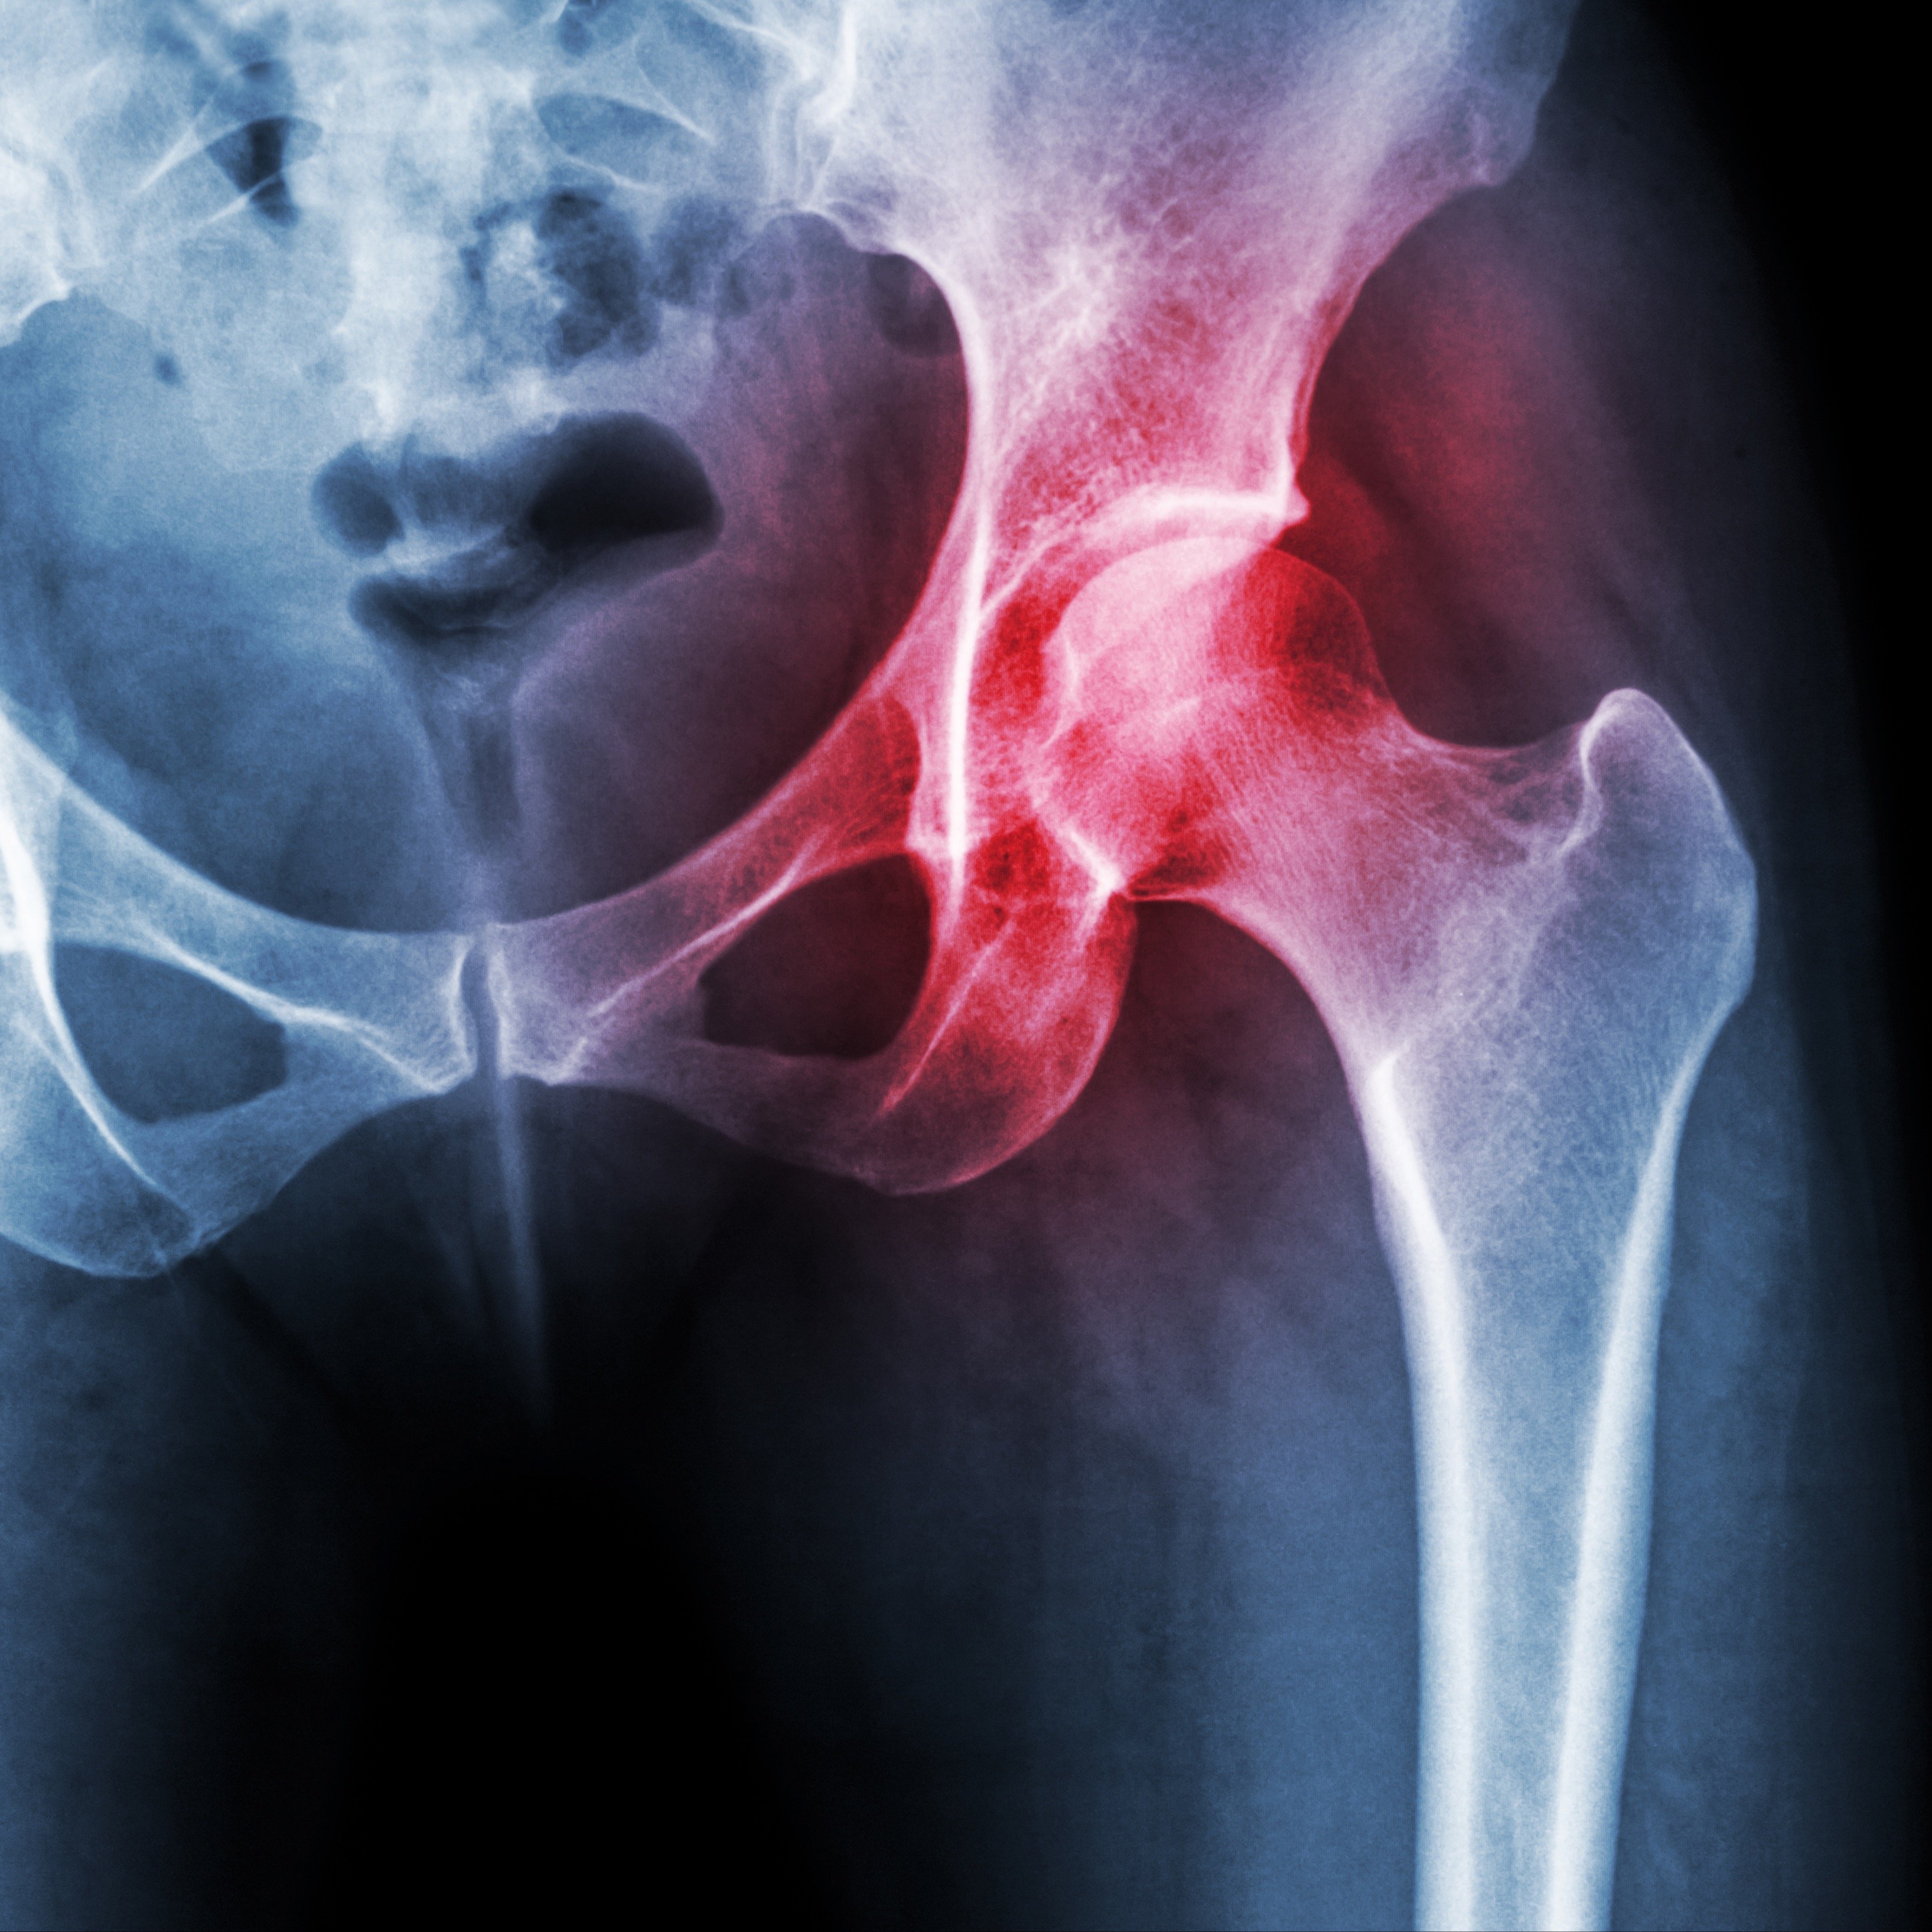

Hyperbaric Oxygen Therapy: A Game-Changer in Avascular Necrosis (AVN) of the Femur

Discover how Hyperbaric Oxygen Therapy (HBOT) revolutionizes the treatment of avascular necrosis (AVN) of the femur, offering a non-surgical path to bone rejuvenation and healing.